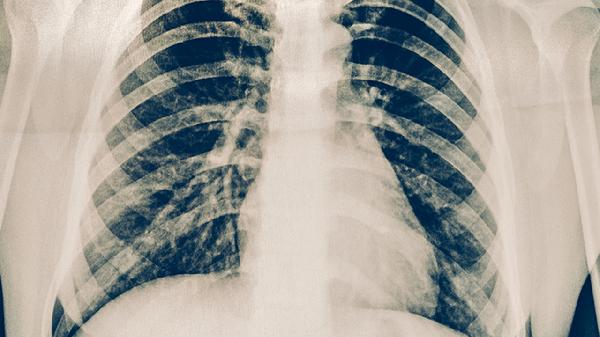

伤后1周、2周、4周分别进行X线复查,观察骨痂生长情况。多发性骨折需每月复查CT直至愈合,延迟愈合者需考虑体外冲击波治疗。康复期逐步开始肩关节环转运动,6-8周后可尝试游泳等低冲击运动。